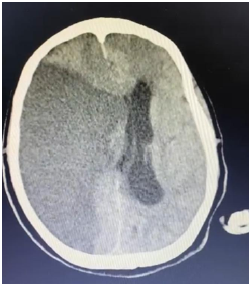

Um paciente de 76 anos de idade deu entrada na UPA, já fora de janela para trombólise, e foi posteriormente encaminhado para a UTI. A imagem apresentada refere-se à tomografia de admissão na UTI.

O paciente evoluiu com morte encefálica. O primeiro exame clínico confirmatório foi realizado às 12 horas, o segundo às 13 horas, e o método gráfico às 23 horas. Sabendo que todos os trâmites legais foram feitos, como notificação compulsória e acompanhamento com a ajuda da comissão intra-hospitalar de doação de órgãos e tecidos (CIHDOTT), qual o horário do óbito e qual a medida esperada?

Supondo que o paciente tenha evoluído com a necessidade de craniectomia descompressiva, e já há mais de 5 dias sem uso de drogas sedativas ou analgésicas, qual seria o método gráfico preferencial para a confirmação da morte encefálica para o referido paciente?

Diagnosticada a hipertensão intracraniana, a conduta mais prontamente adequada seria o uso de

Na UTI, o paciente evoluiu com aumento progressivo dos níveis pressóricos e com bradicardia.

Qual seria o exame mais facilmente disponível nesse momento, para tentar estabelecer um diagnóstico?